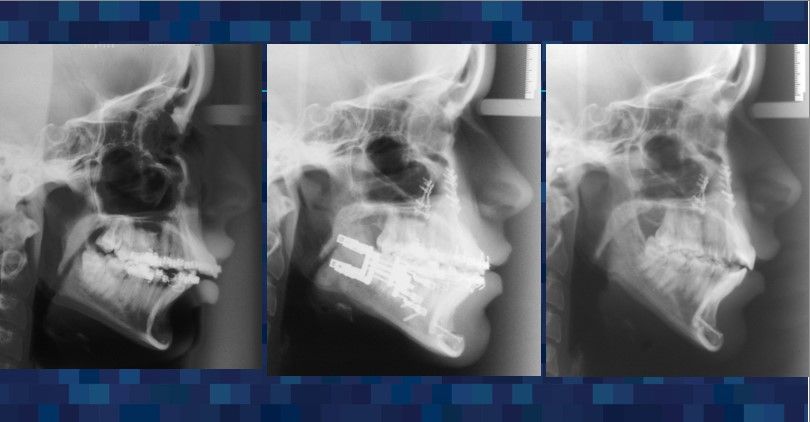

Dr. Cesar Guerrero’s distinguished expertise in oral and maxillofacial surgery and compassionate approach renews patients’ lives by helping them restore function, relieve pain, and rediscover joy.